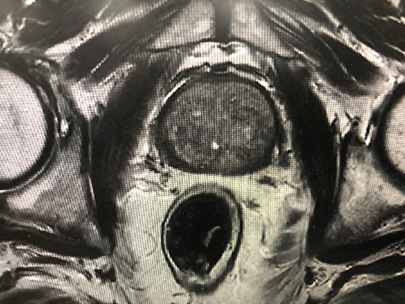

病例一,70岁男性,发现前列腺结节3个月,tPSA 4.66ng/ml,fPSA 0.520 ng/ml,盆腔mri示前列腺结节,Ca?双侧腹股沟多发稍大淋巴结。前列腺穿刺活检示前列腺腺泡腺癌,4针阳性,Gleason评分4+4=8分,行机器人辅助腹腔镜前列腺癌根治术+盆腔淋巴结清扫术,术者:王国良教授。